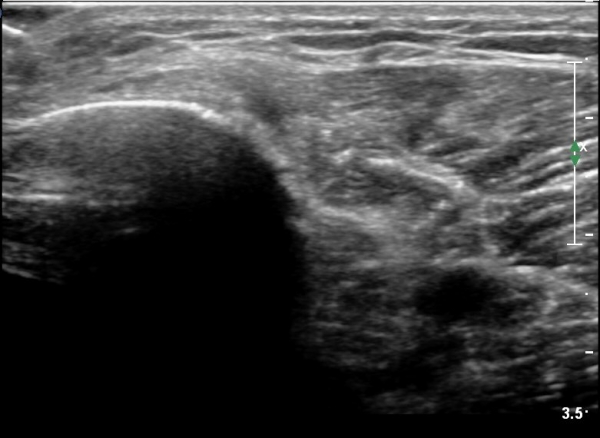

[¹«¸­] °æ°ñ ÇǷΰñÀý ÃÊÀ½ÆÄ¼Ò°ß(sonographic findings of stress fracture of tibia)

¾Æ·§´Ù¸® Áß°£ ºÎÀ§¿¡ °æ¹ÌÇÑ ¿¬ºÎÁ¶Á÷ ºÎÁ¾ÀÌ °üÂûµÇ°í ¾à°£ÀÇ ±¹¼ÒÀû ¾ÐÅëÀ» º¸ÀÓ.

ÃÊÀ½ÆÄ °Ë»ç

¹Ì¼¼ÇÏ°Ô ¿¬ºÎÁ¶Á÷ ºÎÁ¾°ú °¡°ñ Çü¼ºÀÌ °üÂûµÊ.

Bilateral stress fracture of the tibia diagnosed by ultrasound. A case report